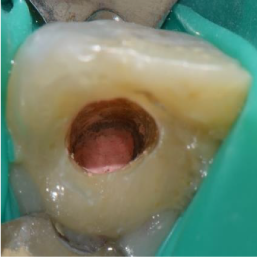

To fit the MTA in the apical portion, 2 Machtou pluggers number 2 and number 4 were chosen (silicone stop must be at WL – 2mm and at Working Length(WL) – 4 or 5mm respectively with a slight contact with root walls). The powder of MTA (Dental Tulsa Dentsply) was mixed with sterile water (figure 2a) following the manufacturer’s instruction.Then, the mixture was carried into the canal using an amalgam carrier and genteelly condensed apically to create an apical plug of 4-5 mm of thickness. To check the correct position of the MTA mixture, an X-ray control was done immediately (figure 2b). A wet cotton pellet with sterile water was then placed in the pulp chamber and the access cavity was temporary sealed with IRM (Caulk/Dentsply, Milford, DE, USA). Two weeks later, the tooth was asymptomatic, so the rest of the canal was obturated with thermoplasticized gutta-percha (Revo®condenser, MicroMega). The final result of the obturation can be seen in figure 2c.

Figure 2a. MTA mixed with sterile water following the manufacturer’s instructions

Figure 2b. Immediate postoperative periapical radiograph

Figure 2c. Postoperative periapical radiograph of the canal obturation